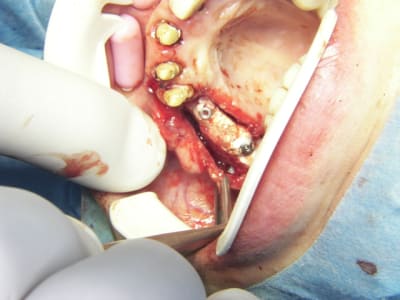

bon et bien ça c'est fait!

curetage (deux bonnes heures) dépose des deux vis d'ostéo et de l'implant en 16, nettoyage implant en 14/15 (axe un peu limite pour cause structure osseuse) et 17.

Vitalos

le greffon placé il y a 6 mois (grosse corticale) était dans le "vide" au niveau de 14, et il m'aurait fallu le piezzo éventuellement (il n'était pas installé, pour cette chir) pour "percer" la corticale sans pression, car à la fraise, je sentais le bloc plier, et nous avons préférés (avec le confrère) tenter un compromis pour la prothèse qui ne sera pas catastrophique et devrait permettre à la patient (qui a déjà subie 2 greffes, menton et ramique, avec un souvenir sympa du menton d'ailleurs)d'avoir une reconstruction fixe.

je ne sais pas si le vitalos permettra de rattraper ce cas là, mais vu tous les soucis que nous avons rencontrés pour le nettoyage (biooss infiltré dans la muqueuse de partout, j'ai du "virer" 60% du périoste et honnêtement je ne savais pas trop comment faire un "abri" de reconstruction pour l'os et l"environnement tissulaire, de façon simple.

photos montrant le hiatus greffe/os et pose avec vitalos à la fin